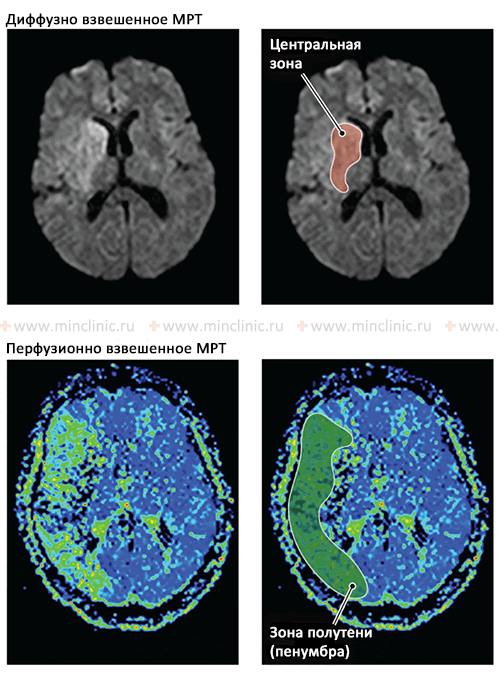

До лечения антикоагулянтами больному следует провести магниторезонансную (МРТ) или компьютерную томографию (КТ) головного мозга. Это исключит небольшое кровоизлияние, обусловливающее такие же симптомы, что и эмболический инсульт.

Люмбальная пункция с целью обнаружения эритроцитов в спинномозговой жидкости (ликворе) показана только в тех случаях, когда предполагается малый (возможно, геморрагический) инфаркт в области моста, сопровождающийся дизартрией, синдромом неловкой кисти или другими синдромами задней черепной ямки. В связи с костными артефактами при компьютерной томографии (КТ) головного мозга у пациента можно «пропустить» кровоизлияние, принять его за малый инфаркт. Проводя магниторезонансную (МРТ) головного мозга пациенту, можно отличить острое кровоизлияние от хронического и от инсульта, получить более надежные данные для раннего выявления инфаркта мозга.

Если диагноз эмболии мозговой артерии обоснован и необходимо установить ее предполагаемый артериальный источник, оправдано проведение церебральной ангиографии. Однако через 24 ч эмбол может подвергнуться переносу, растворению (лизис), расщеплению, и заключение об эмболии как причине эмболического инсульта становится лишь предположительным. Внутривенная контрастная ангиография не обладает достаточной разрешающей способностью для выявления церебральных эмболии.